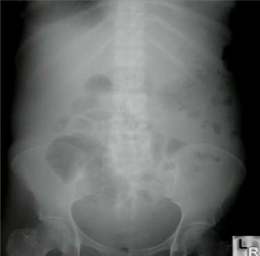

How do you know if you are looking at a supine abdominal view?

Pubic symphysis